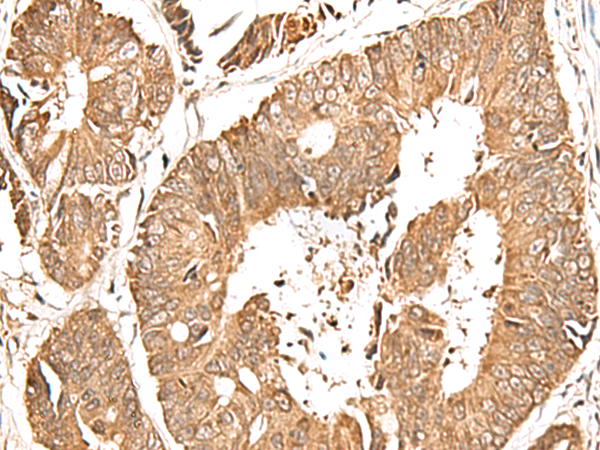

分类: 科研抗体货号: P13457别名: TAMALIN应用: IHC反应种属: Human, Mouse, Rat